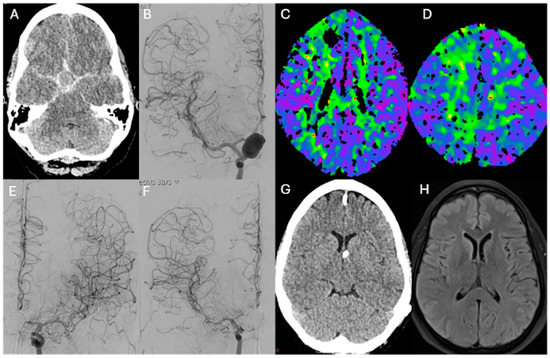

12 pages, 8803 KB

Early Onset of Cerebral Vasospasm and the Mediating Impact of Secondary Infarction on In-Hospital Mortality Following Aneurysmal Subarachnoid Hemorrhage

by Gregor Peter, Lukas Meyer, Bogdana Tokareva, Gabriel Broocks, Matthias Bechstein, Vincent Geest, Christian Heitkamp, Felix Schlicht, Luca Meucci, Lasse Dührsen, Hanno S. Meyer, Helge Kniep, Maxim Bester, Jens Fiehler and Christian Thaler

Diagnostics 2026, 16(4), 551; https://doi.org/10.3390/diagnostics16040551 - 13 Feb 2026

Background: Cerebral vasospasm (CV) as a complication after aneurysmal subarachnoid hemorrhage (aSAH) is a major determinant of secondary vasospasm-associated ischemic infarction (SVS-I) and poor outcome. Data on the interplay among the onset of CV, SVS-I, and in-hospital mortality remain limited. Methods: We conducted [...] Read more.

Background: Cerebral vasospasm (CV) as a complication after aneurysmal subarachnoid hemorrhage (aSAH) is a major determinant of secondary vasospasm-associated ischemic infarction (SVS-I) and poor outcome. Data on the interplay among the onset of CV, SVS-I, and in-hospital mortality remain limited. Methods: We conducted a retrospective, single-center study including patients admitted with aSAH between January 2016 and May 2024 who developed treatment-relevant CV. The primary outcome was the rate of in-hospital mortality. The relationship between the onset of CV, demographics, imaging, and treatment data and the primary outcome was analyzed using logistic regression. A confounder-adjusted mediation analysis was performed to quantify the extent to which the effect of time to CV onset on in-hospital mortality was mediated by SVS-I. Results: A total of 165 patients with aSAH and treatment-relevant CV were included. The median age was 55 (IQR, 48–64), and 67.2% (111) were female. Of the included patients, 13.3% (22) died during hospitalization. In multivariable logistic regression analysis, earlier onset of treatment-relevant CV (adjusted odds ratio [aOR] 0.79; 95% CI, 0.66–0.95) and the occurrence of SVS-I (aOR 13.47; 95% CI, 2.78–65.3) were associated with the primary outcome. Mediation analysis indicated that SVS-I accounted for 28% of the effect of earlier onset of CV on in-hospital mortality. Conclusions: Twenty-eight percent of the effect of earlier onset of cerebral vasospasm on in-hospital mortality was mediated by secondary ischemic infarction. Targeting patients with early-onset vasospasm and the associated risk of infarction may reduce in-hospital mortality following aneurysmal subarachnoid hemorrhage. Full article

(This article belongs to the Special Issue Innovations in Neurovascular Disease Imaging and Treatment)

Show Figures

Figure 1